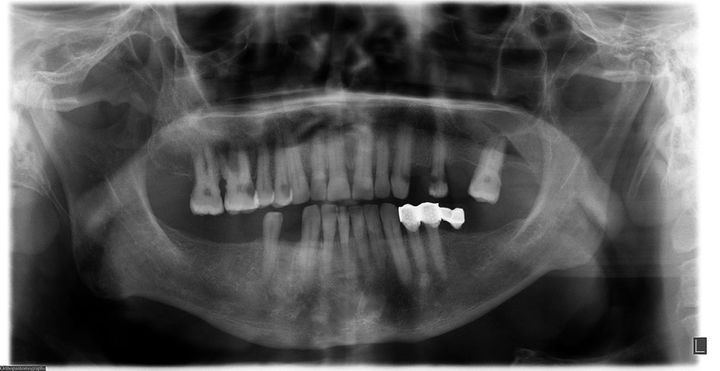

Resim2.1.jpg

Resim2.jpg